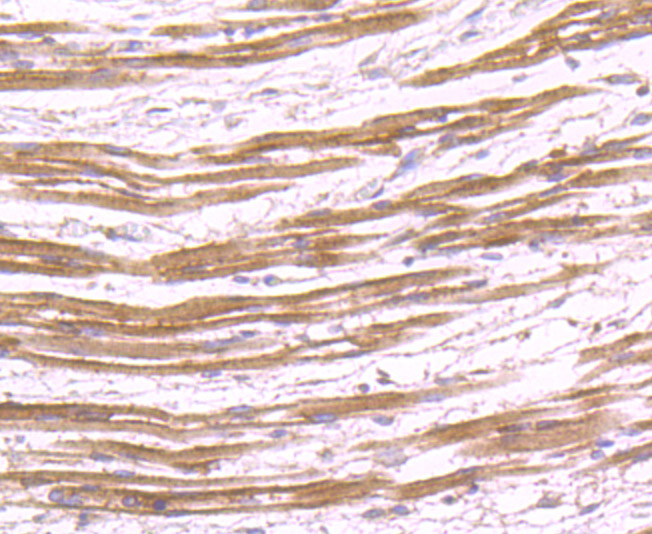

Immunohistochemical analysis of paraffin-embedded human fetal skeletal muscle tissue using anti-SHP2 antibody. Counter stained with hematoxylin.